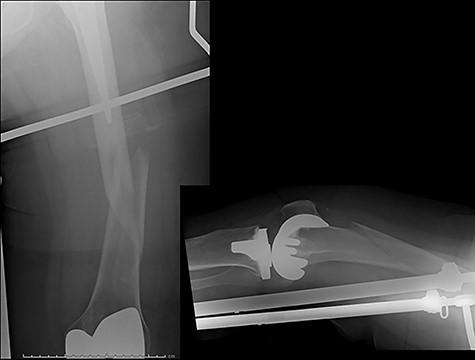

The cases of failure are here examined in more detail. Case 1 (Figs 1 and 2): this active gentleman was paddleboarding off the Llŷn peninsula when he was knocked onto his side by a wave.

Fracture above plate tip following successful union for Case 1.

Clearly, this has occurred following on from successful union. Despite a sound original fixation, the rigid construct has acted as a lever-arm to produce a fracture above the plate tip. In long spiral fracture configurations such as this, antegrade intra-medullary nailing could be considered as the primary treatment modality.